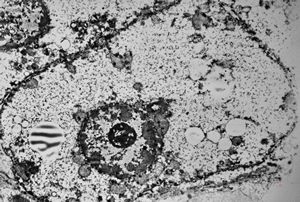

M, 1y. | glycogenosis type I. - liver